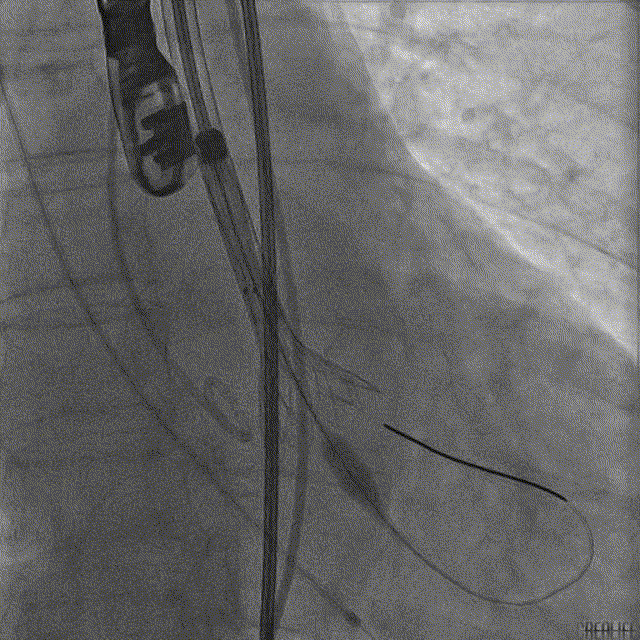

TaurusOne® 输送器顺畅过弓

造影辅助定位

精准释放